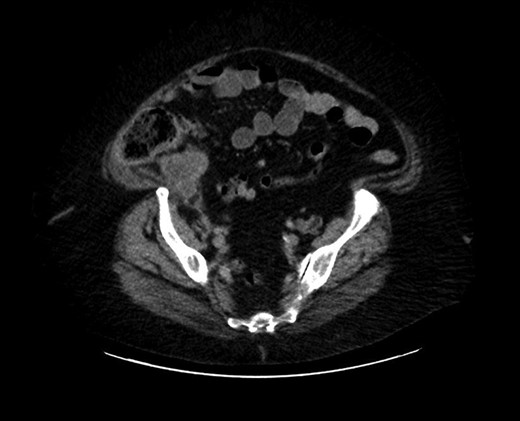

The cecum measures 8 × 6 cm and appendix is dilated and measures 7 cm × 2 cm. The mucosa at the appendicular orifice demonstrates a polypoid appearing mass measuring 3.2 × 1.5 cm (Fig. 3). Grossly the mass extends throughout the appendix and measures approximately 7.7 cm × 2 cm. The distal aspect was hemorrhagic and ragged, with an opened ragged defect measuring 1 cm in greatest dimension (Fig. 4). The majority of the appendicular serosa was tan and smooth, with scattered red areas. Grossly, the tumor is 1.5 cm from the mesenteric margin. Multiple lymph node candidates are identified. One lymph node candidate measures up to 5 mm and is 4 mm from the mesenteric margin.

A longitudinal cross section of the appendix, adenoma at appendiceal orifice on left, hemorrhagic tip rupture on right.